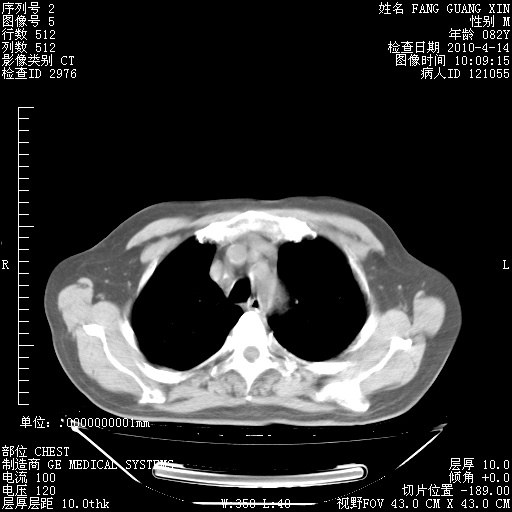

4月14日肺部CT